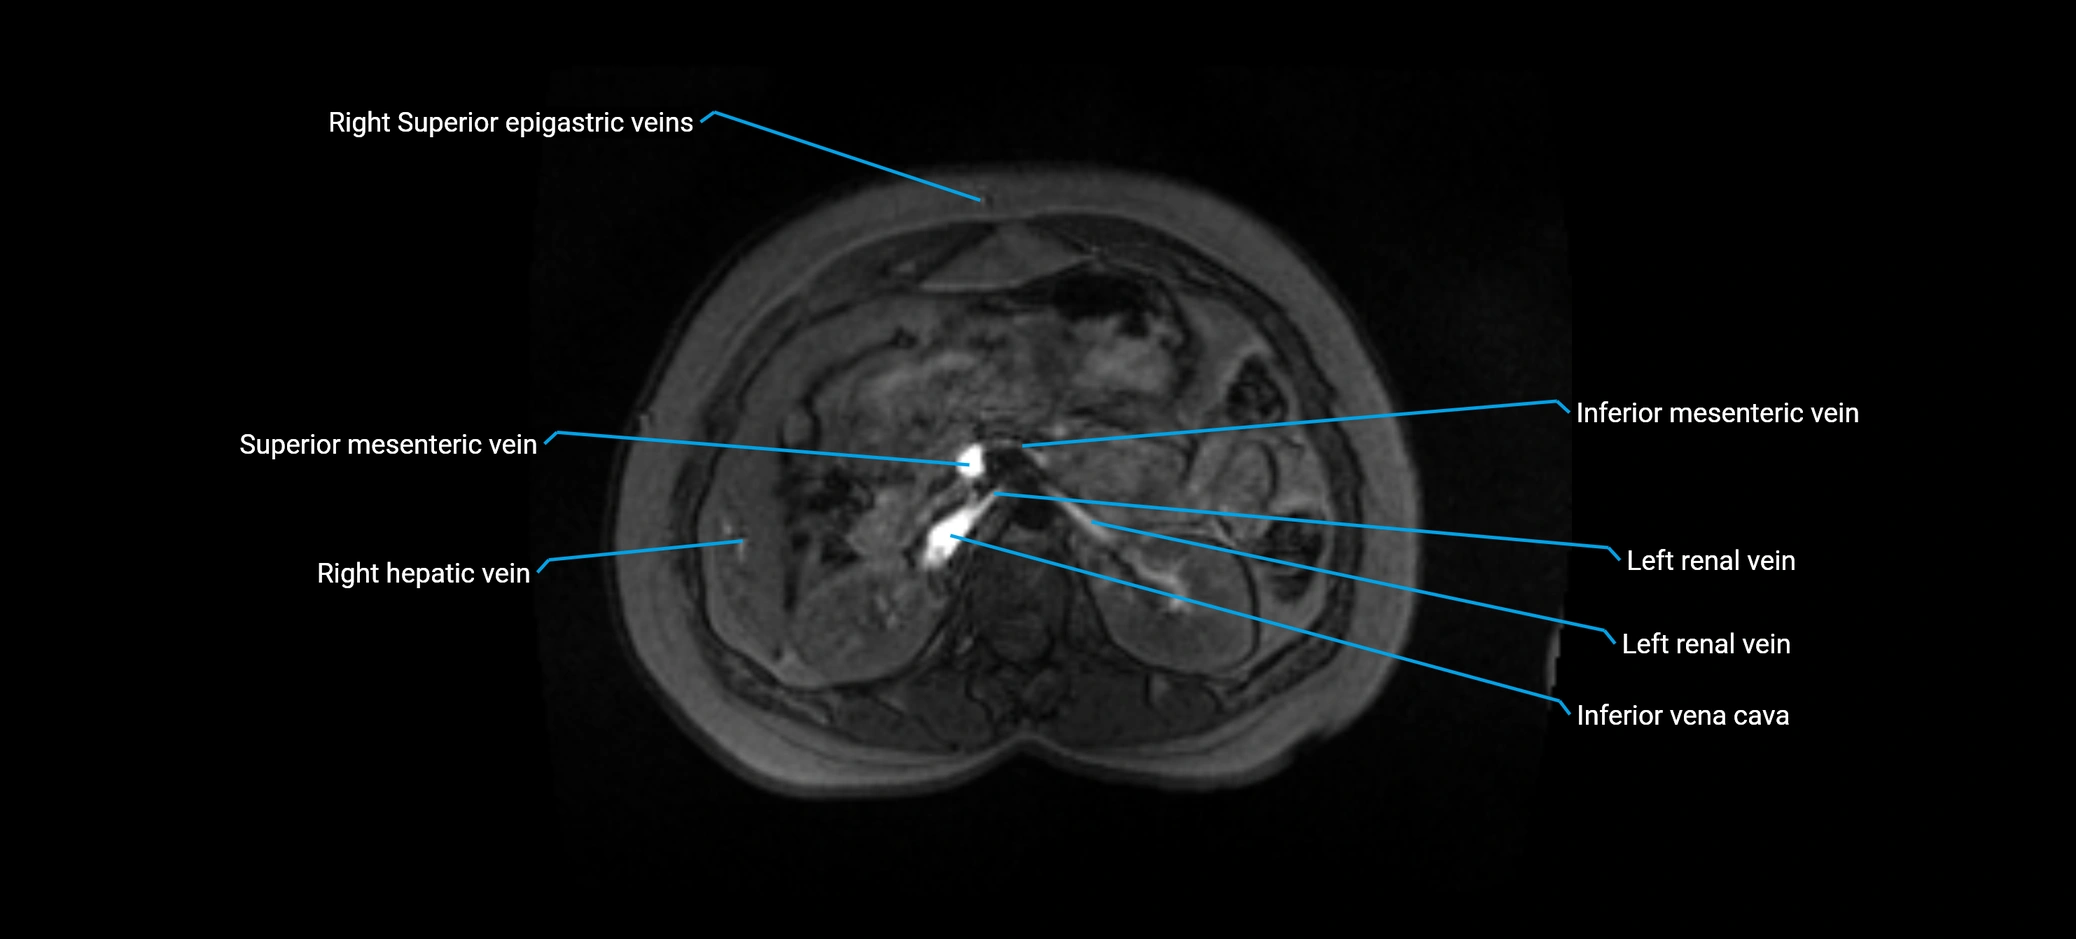

MRI image

image